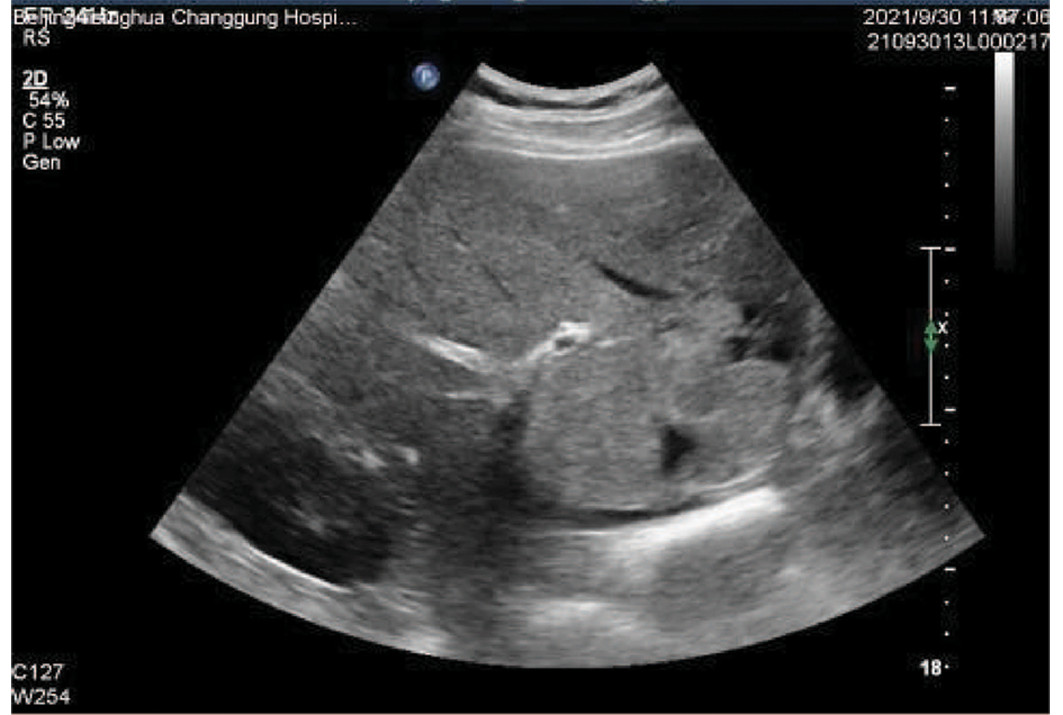

先天性左肝缺如合并肝细胞癌1例报告

王海林, 李敬东, 武国

2023, 39(6): 1408-1410. DOI: 10.3969/j.issn.1001-5256.2023.06.023

摘要(836) HTML (197) PDF (2003KB)(59)

摘要: